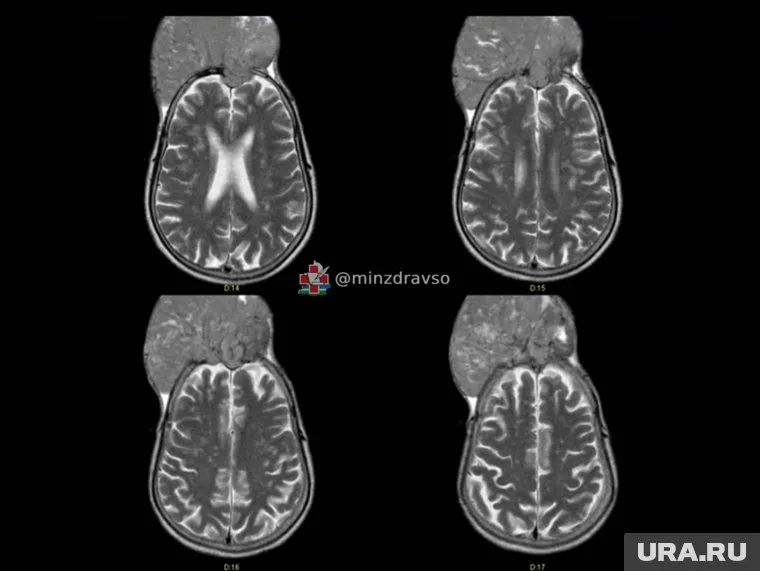

Специалисты Свердловского областного онкологического диспансера успешно провели сложную операцию по удалению гигантской менингиомы у жителя Краснотурьинска. Опухоль крыла клиновидной кости достигла размеров 15 на 15 сантиметров и буквально разрушила часть черепа пациента.

В случае с краснотурьинцем опухоль проросла в кости черепа и вышла наружу, но долгое время не вызывала выраженных симптомов, что затруднило своевременное обращение за медпомощью. Лечение началось с малоинвазивной процедуры — рентгенэндоваскулярные хирурги «выключили» сосуды, питающие опухоль, чтобы минимизировать кровопотерю при последующем вмешательстве. «Специалисты Свердловского областного онкологического диспансера спасли краснотурьинца с менингиомой крыла клиновидной кости, которая буквально „съела“ череп», — говорится в сообщении официального telegram-канала свердловского минздрава.

Фото: Фото: telegram-канал свердловского минздрава